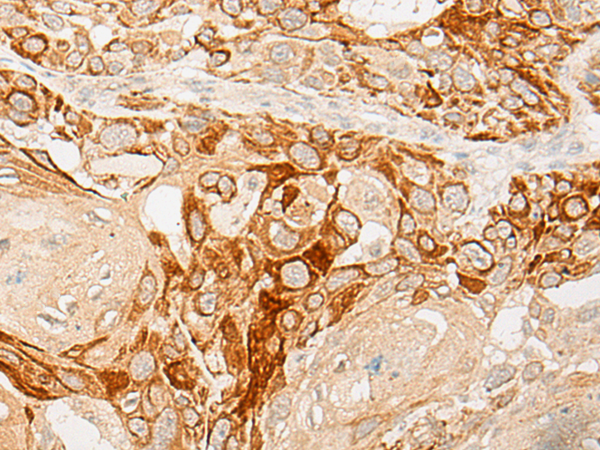

IHC Positive control: |

Human esophagus cancer;Human liver cancer |

IHC Recommended dilution: |

25-100 |